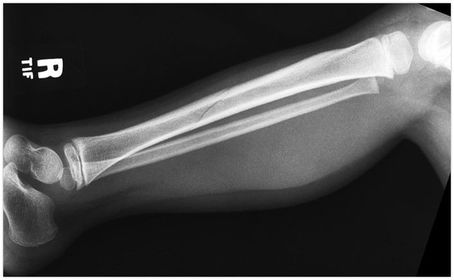

AP Tib/Fib 40 SID 14x17 IR tabletop - pt supine w/ leg rotated inward 5 degrees w/ foot dorsiflexed for TRUE AP - CR perpendicular @ midleg *must see ankle and knee joints on image - you can overlap 2 images if 1 doesn't fit both joints*

Lateral TIb/Fib Mediolateral 40 SID 14x17 IR tabletop can angle IR diagonally to fit entire tib/fib on - CR perpendicular @ midleg *must see ankle and knee joints on image - you can overlap 2 images if 1 doesn't fit both joints*